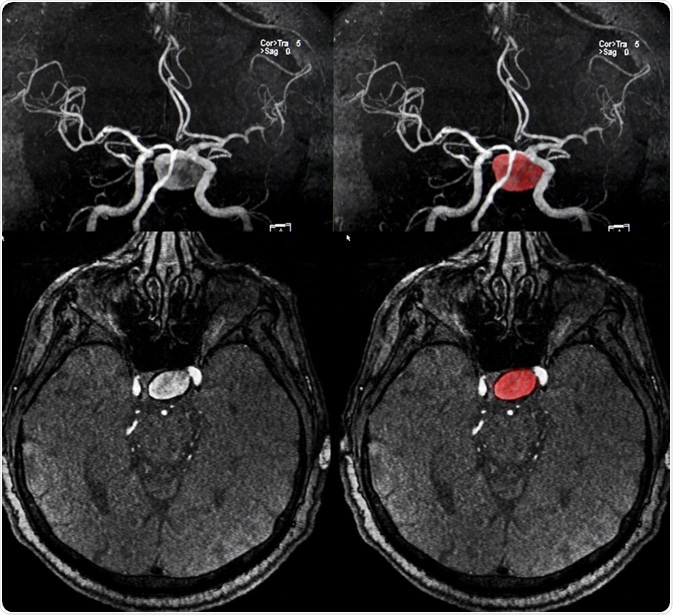

A brain (cerebral) aneurysm is a weak spot in an artery in the brain that swells and fills with blood.

Image Credit: Semnic / Shutterstock.com

The bulging area within a cerebral aneurysm can put pressure on surrounding tissue or a nerve. The aneurysm can also rupture, spilling blood into the brain tissue. This is referred to as a subarachnoid hemorrhage.

In most cases, a cerebral aneurysm does not cause any symptoms and goes unnoticed; however, in rare cases, the aneurysm ruptures, causing a hemorrhage and stroke. Depending on how severe the hemorrhage is, a person may suffer brain damage or even die. Cerebral aneurysms can occur anywhere in the brain, but the most common location is a loop of arteries found at the base of the brain, referred to as the circle of Willis.